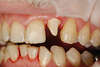

Cette incisive a été fracturée suite à un accident                                                                                                                    Il a été possible de la remplacer par un implant

incisive fracturée